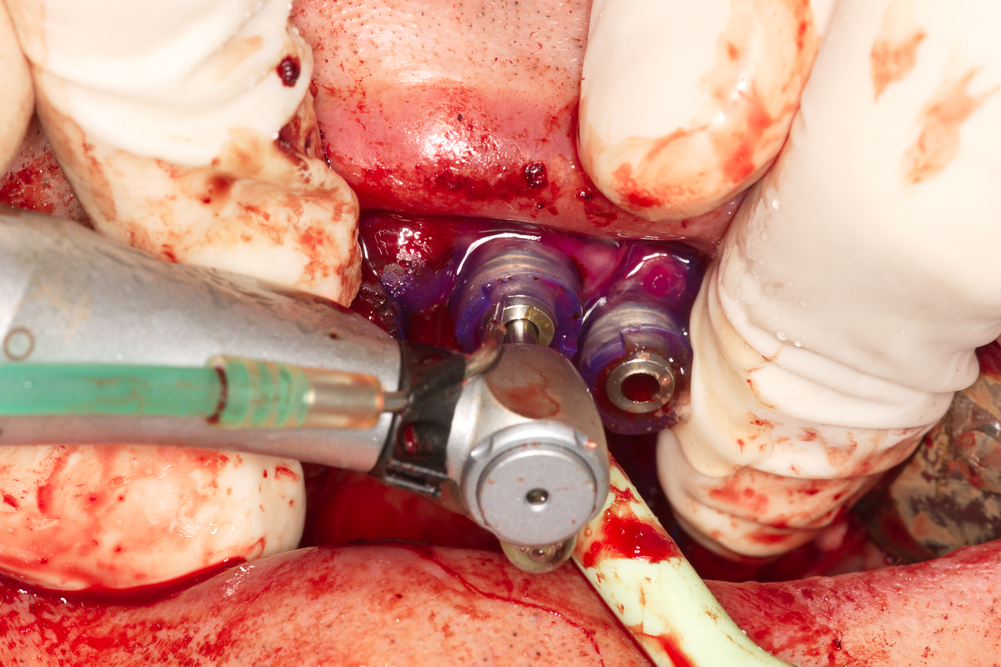

Изключително показателна снимка. Вижда

се хирургичен водач от последно поколение - налице е метална втулка, която

фиксира абсолютно точно положението на фрезите от първата до последната, а също

така и на самия зъбен имплант. Формата на металната втулка съответства абсолютно

точно на едно цилиндрично удебеление в основата на хирургичната фреза - като

това удебеление е еднакво при всички видове фрези, а също и при свързващите

елементи за завинтване на самата имплантатна платформа. това осигурява

максимално възможната точност в трите пространствени измерения.

Горната снимка обаче е показателна и за нещо съвсем различно от позиционирането

на импланта. При

разпробиването и калибровката на костта е необходима силна и постоянна иригация,

която при повечето имплантологични юнити на пазара е осигурена безпроблемно.

Лошото е че при употребата на хирургичен водач се охлажда втулката на водача, а

не костта на пациента - което и се вижда отлично на заснетото от нашия екип

изображение. Различни

лабораторни проучвания показват че всъщност проблем няма - експерименталните

модели не регистрират температурни разлики в предела на костните тъкани

непосредствено до разпробития отвор. За съжаление обаче условията ин виво и ин

витро не винаги са едни и същи - повечето лабораторни проучвания са извършени

върху пластмасови модели, тъй като правителствените директиви ограничават

експериментите върху животни. Костната тъкан обаче отделя различни по големина

отпилки, които зацапват пилителите и затрудняват разпробиването и калиброването

на костта. Пластамсовите отпилки имат доста по-различни физико - механични и

химични свойства. Поради това много зъботехнически лаборатории вече изработват

хирургични водачи с допълнитено разпробити иригационни отвори - използва се така

наречената трипътна (или дори четирипътна) канюла, която свързва допълнителни

охладителни маркучи към предварително проектирани иригационни отвори в

пластмасата на водача. По този начин се осигурява максимално ефективна иригация

на оперативното поле и локалната температура не се повишава. Оказва се че нашият

екип отново е подвел аудиторията - хирургичният водач на горната снимка НЕ Е от

последно поколение, а всъщност от предпоследно. За кой ли път, за кой ли път -

както пеят Фамилия Тоника, извиняваме се за погрешната информация, но очевидно

случката ще се повтори и потрети. При загряване на

костта до 46 градуса на практика проблем няма - не може да се оформи участък на

костна некроза. При повишаване на локалната температура само с един градус обаче

(до 47 по скалата на Целзий) вероятността от термични увреждания нараства два

пъти.